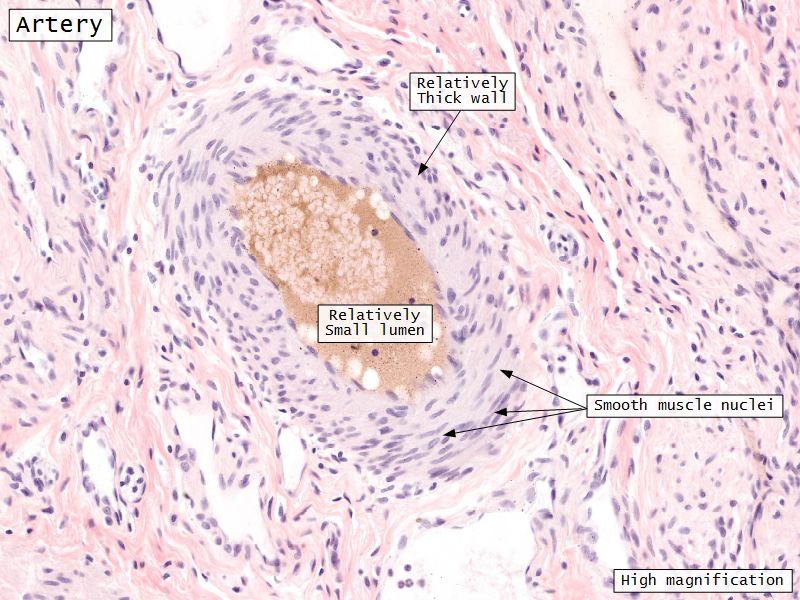

Medulla

- Blood vessels

Blood vessels

- Enter medulla at hilus

- Supply the cortex

Blood supply

- Originate from myometrium

- Helical arteries

- Extend into functional layer

- Straight arteries

- Terminate basal layer

- AVN

- Leydig cells

Leydig cells

- Interstitial cells

- Surrounded by rich AVL

- Large round - polygonal shape with clear cytoplasm

- Large central nucleus

- Endocrine - testosterone